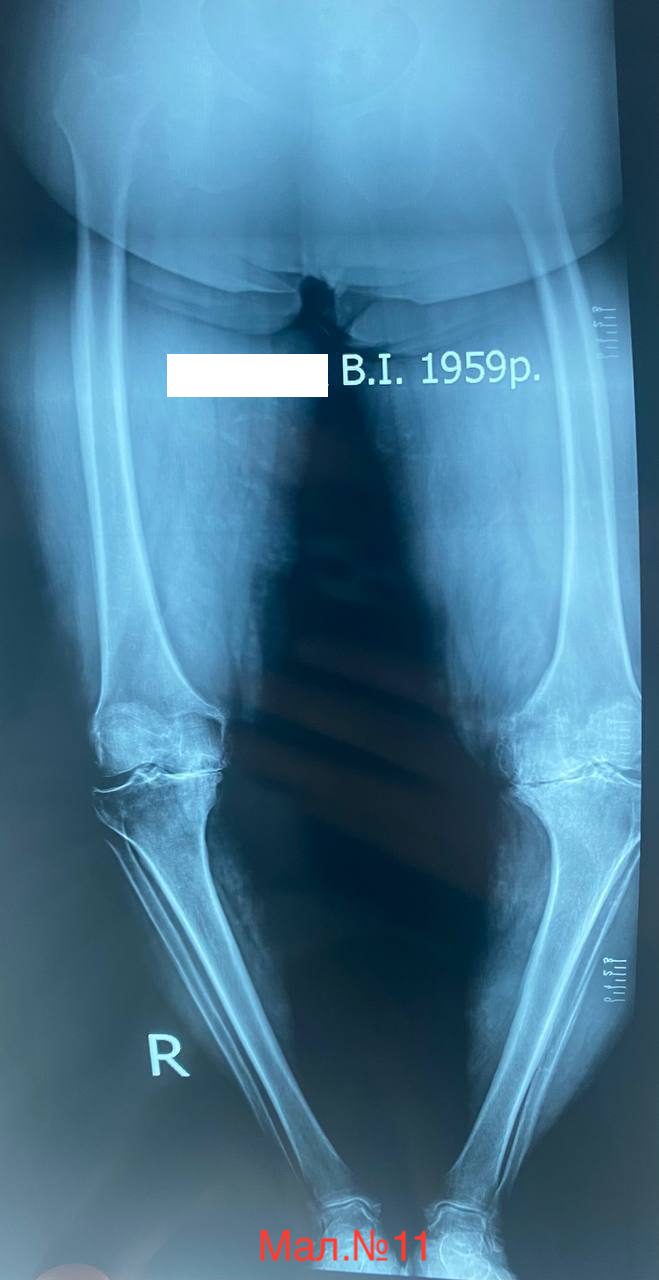

photo_2023-12-13 17.11.07